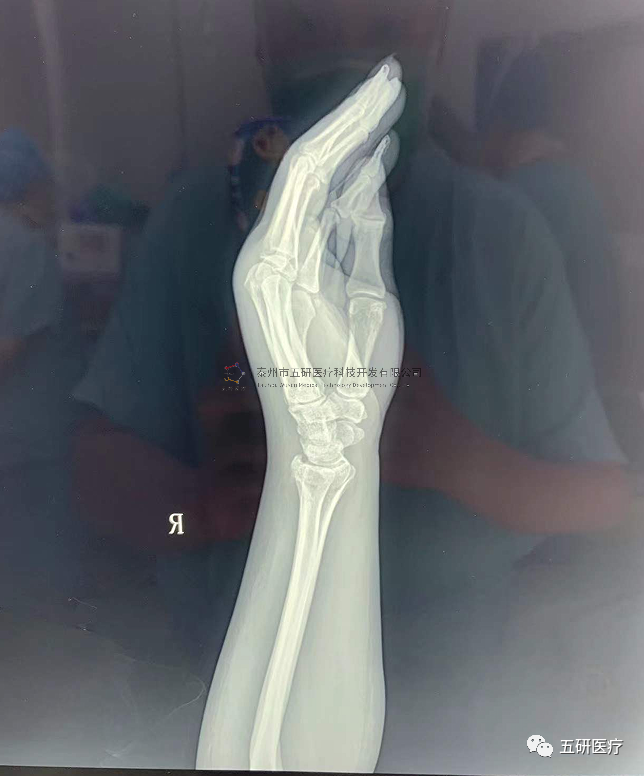

// 腕架

本病例由中國(guó)中醫(yī)科學(xué)院望京醫(yī)院骨綜科提供(術(shù)者:支架醫(yī)生常醫(yī)師)

【基本資料】患者,女,61歲

本病例腕架骨折。術(shù)前正側(cè)位片:右橈骨遠(yuǎn)端骨折。

采用常規(guī)方法固定,自掌骨尺側(cè),約基底稍偏遠(yuǎn)處穿入螺紋針。

外架馬蹄環(huán)穿過(guò)骨針,更方便調(diào)整固定角度。